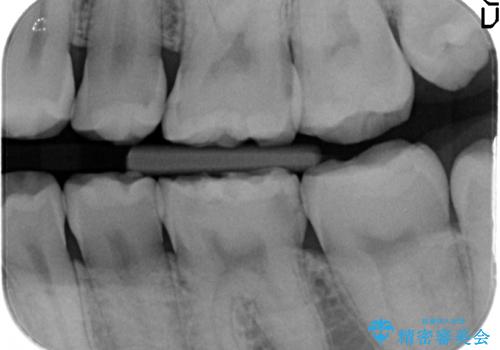

- 冷たいものを飲むと、左下奥歯がしみると来院された方の症例です。

検査の結果左下6が虫歯になっていたため、セラミックインレーによる修復を行いました。